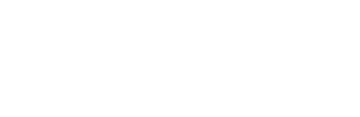

Ontdek het pad van de nerf sciatique en verlicht je pijn

De nervus ischiadicus, of nerf sciatique, is de grootste zenuw in het menselijk lichaam en essentieel voor het functioneren van de benen. Het begrijpen van het traject is cruciaal voor het identifi...

Ontdek de verborgen signalen van sciatique in je rechterbeen en vind verlichting

Sciatique, vaak veroorzaakt door druk op de nervus ischiadicus, leidt tot pijn die van de onderrug naar het rechterbeen uitstraalt. Vroege herkenning van symptomen, zoals brandende pijn en tintelin...

Verlicht je pijn: ontdek de geheimen van de nerfs sciatique

De sciatische zenuw, de grootste in het menselijk lichaam, is essentieel voor mobiliteit en gevoel in de benen. Problemen met deze zenuw kunnen leiden tot sciatique, gekenmerkt door pijn, tinteling...